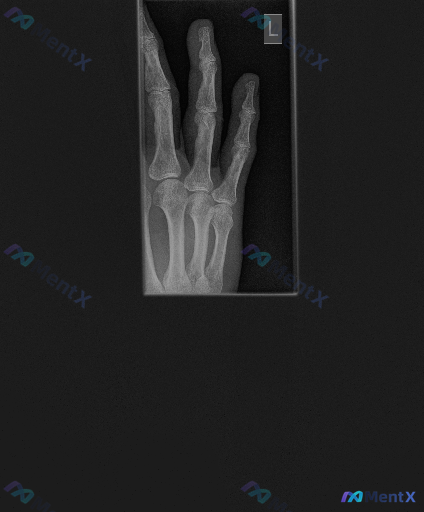

左手手指X光见关节间隙狭窄+虫蚀样改变,第一眼会先考虑哪类问题?

核心影像表现:

- 中指及无名指近节指间关节(PIP)间隙狭窄,中指尤为明显

- 部分关节面边缘骨质改变,不够光滑,可见边缘骨赘形成

- 关节面边缘有不规则虫蚀样/缺损样骨质改变,骨密度不均

- 中指PIP关节周围软组织明显梭形肿胀

- 关节周围可见骨质疏松表现,骨皮质相对变薄

- 未见明显痛风石样高密度钙化灶,未见异物或内固定物

这份影像的改变,不是单纯的“磨损”能完全解释的,尤其是虫蚀样侵蚀和梭形肿胀。大家第一眼会先把重心放在哪类鉴别上?